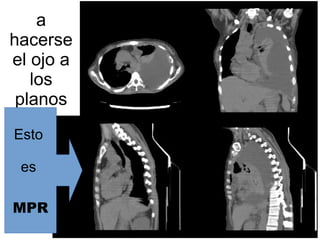

a

hacerse

el ojo a

los

planos

Esto

es

MPR

MPRMPR Reconstrucción Multiplanar

Es una deformación geométrica del volumen

de datos. No es 3D.

Suele ser la más utilizada. Permite visualizar el

volumen.

Las reconstrucciones multiplanares deben ser

calculadas a partir de voxels isotrópicos (voxels

con lados iguales en las tres dimensiones del

espacio)